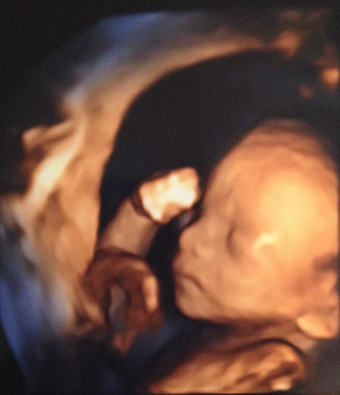

Ultraschallaufnahme menschlicher Embryo

Ultraschallaufnahme eines menschlichen Embryos in der 20. Schwangerschaftswoche. Es gelten die Nutzungsbedingungen der Mediothek und Pixiothek.